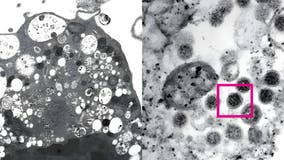

New Omicron subvariant becoming dominant COVID strain in U.S.

A new Omicron variant known as XBB.1.5 is reportedly spreading quickly nationwide as doctors say COVID-19 continues to evolve.